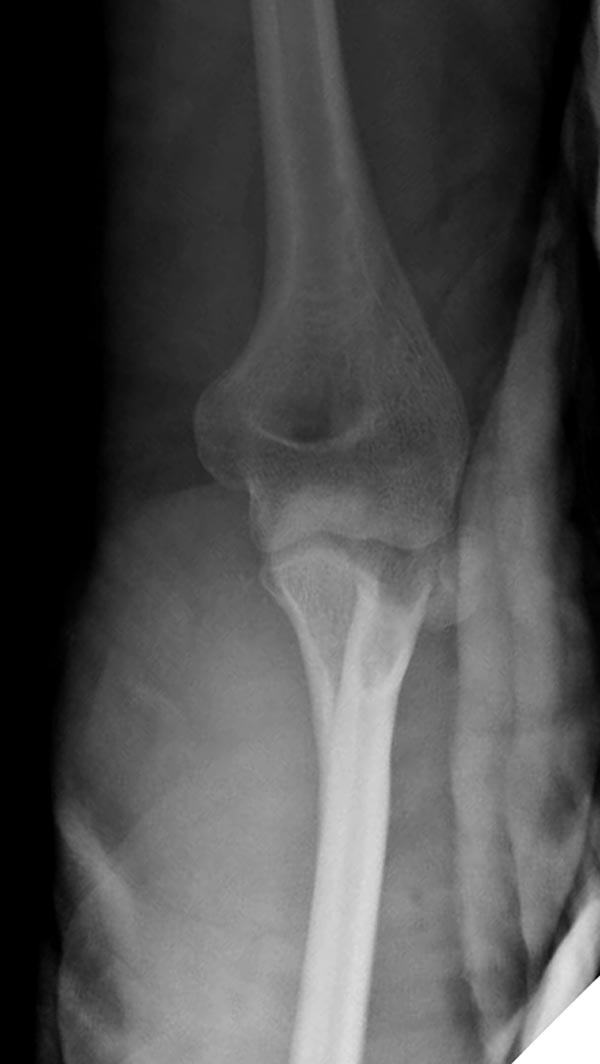

Имя     : 4 Elbow radial head fx.JPG

Тип     : image/jpeg